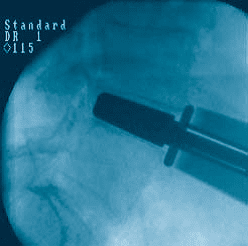

Watch the prodisc L Surgical Technique:

prodisc L Gallery

Click to enlarge image